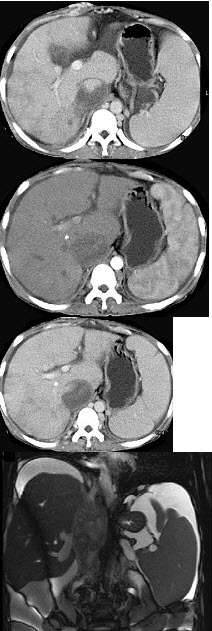

女性,26岁,腹胀不适7月,腹软,肝右肋缘下1cm,影像检查如图,可能的诊断为( )

A:肝血管瘤

B:原发性肝癌

C:肝硬化腹水

D:巴-希综合征

E:脂肪肝